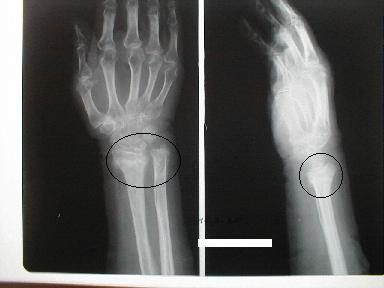

1月21日受傷 正面像

とう骨下端 尺骨茎状突起骨折

皮下溢血、腫脹著明で運動制限有り

側面像